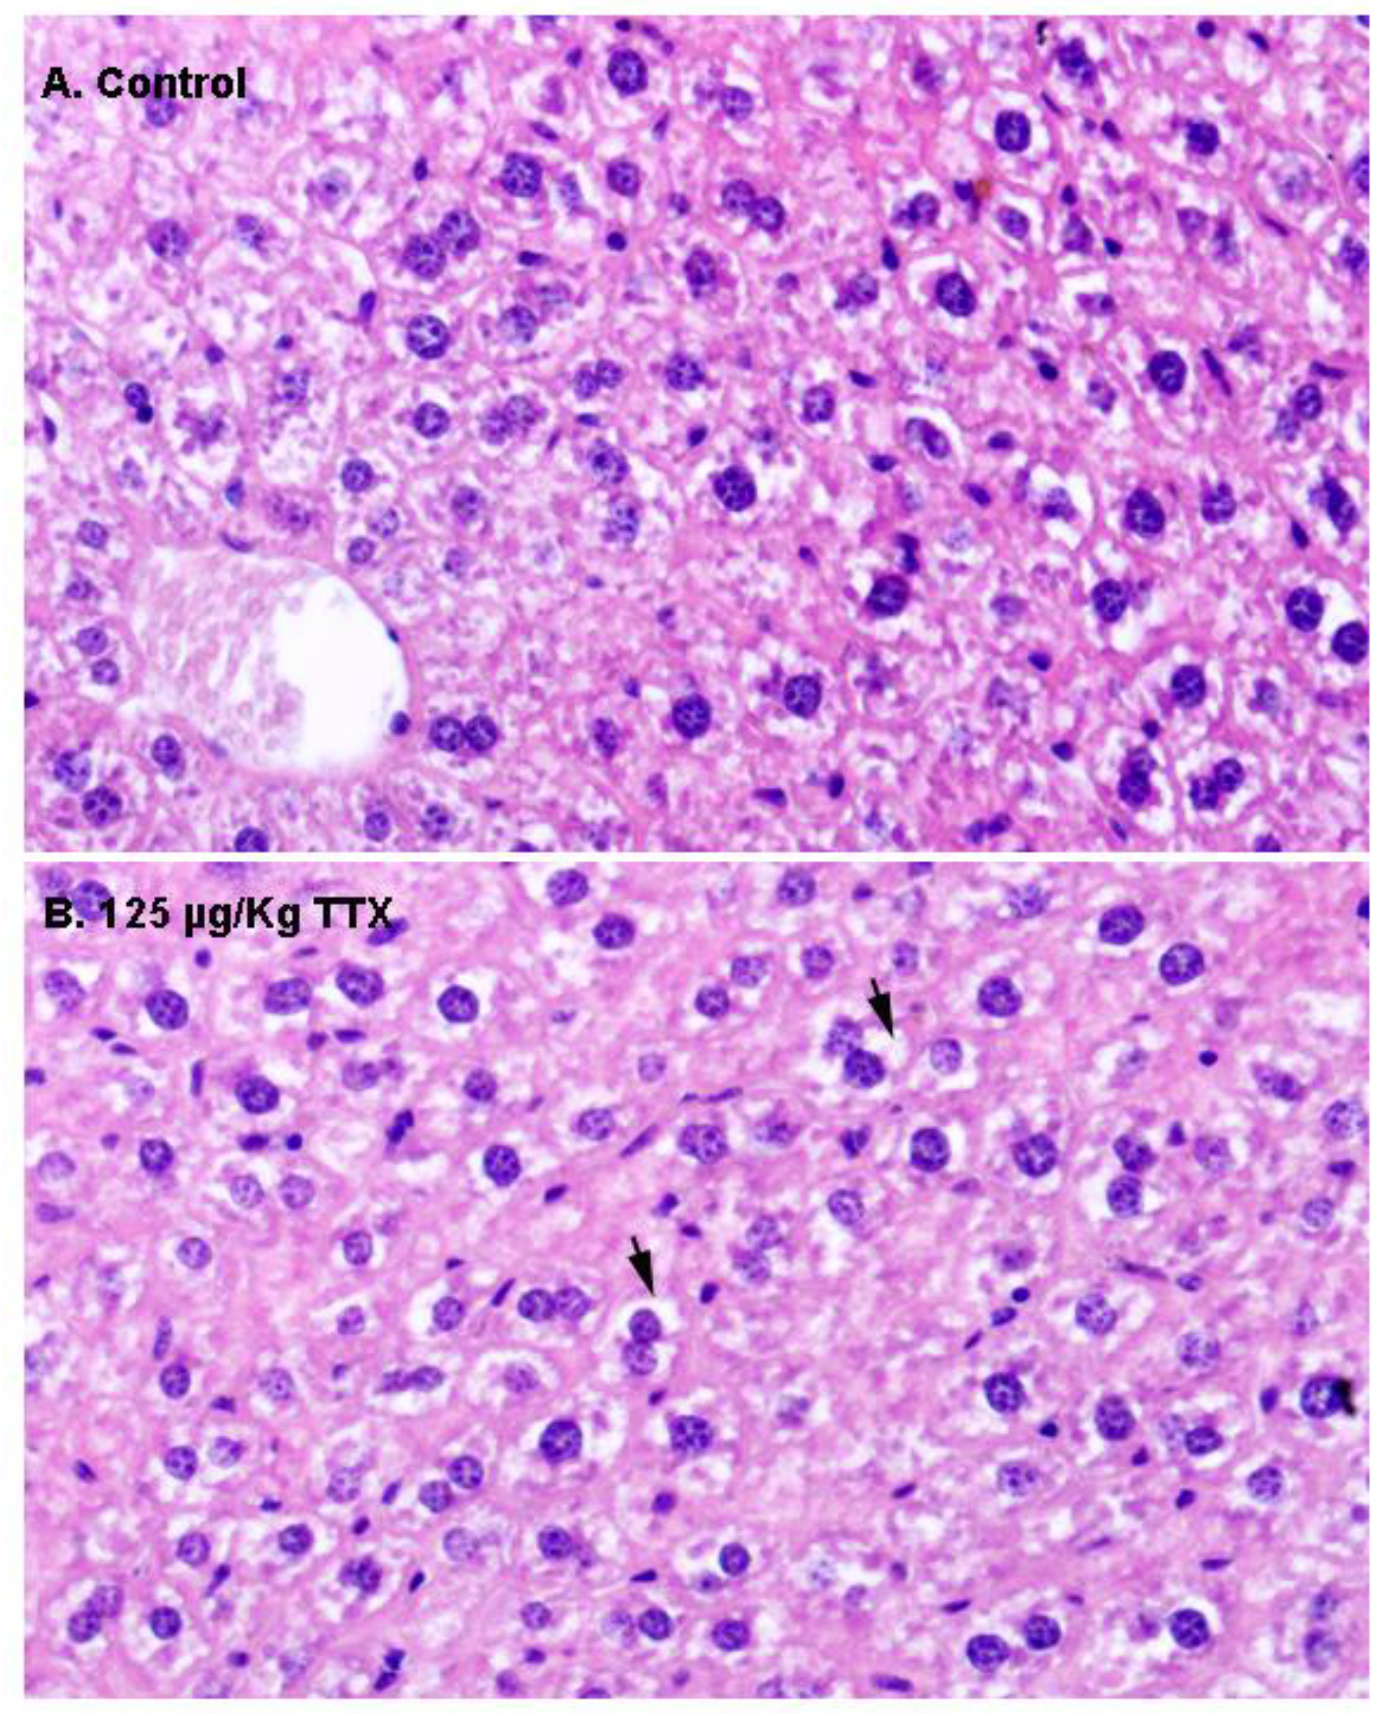

First, liver samples were stained with H&E (Figure 2). In contrast to liver sections from control mice, in which hepatocytes showed an eosinophilic cytoplasm and a round nucleus (Figure 2A), hepatocytes in the livers of mice fed daily with TTX at 125 µg/kg during 28 days showed a more vacuolated (non-stained) cytoplasm (Figure 2B) that could represent cellular swelling, lipid accumulation, or glycogen stores.

Figure 2.

Representative hematoxylin–eosin (H&E) staining of the liver parenchyma in a sample from a control mouse (A), and from a mouse treated with 125 µg/kg oral TTX for 28 days (B). Compared to hepatocytes from control animals, more cytoplasmic vacuoles (non-stained spaces, indicated by arrows) were present in the hepatocytes from TTX-treated mice. In both cases, 600× microscope magnifications are shown.